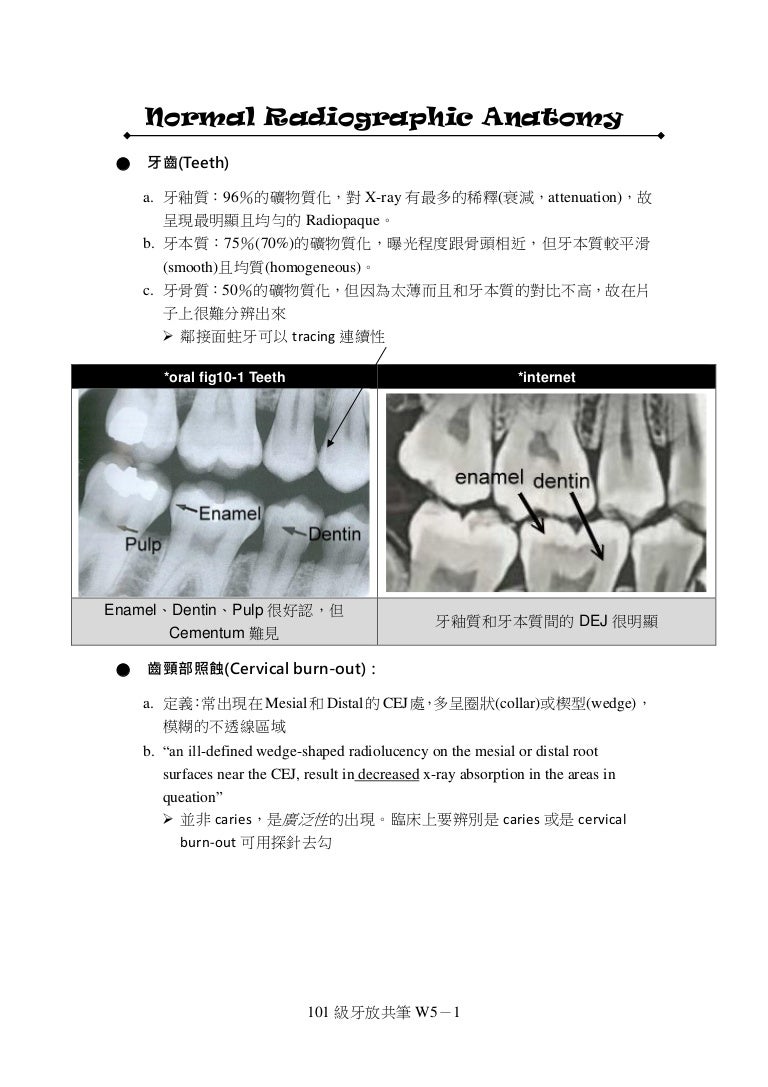

D101 牙放共筆w5